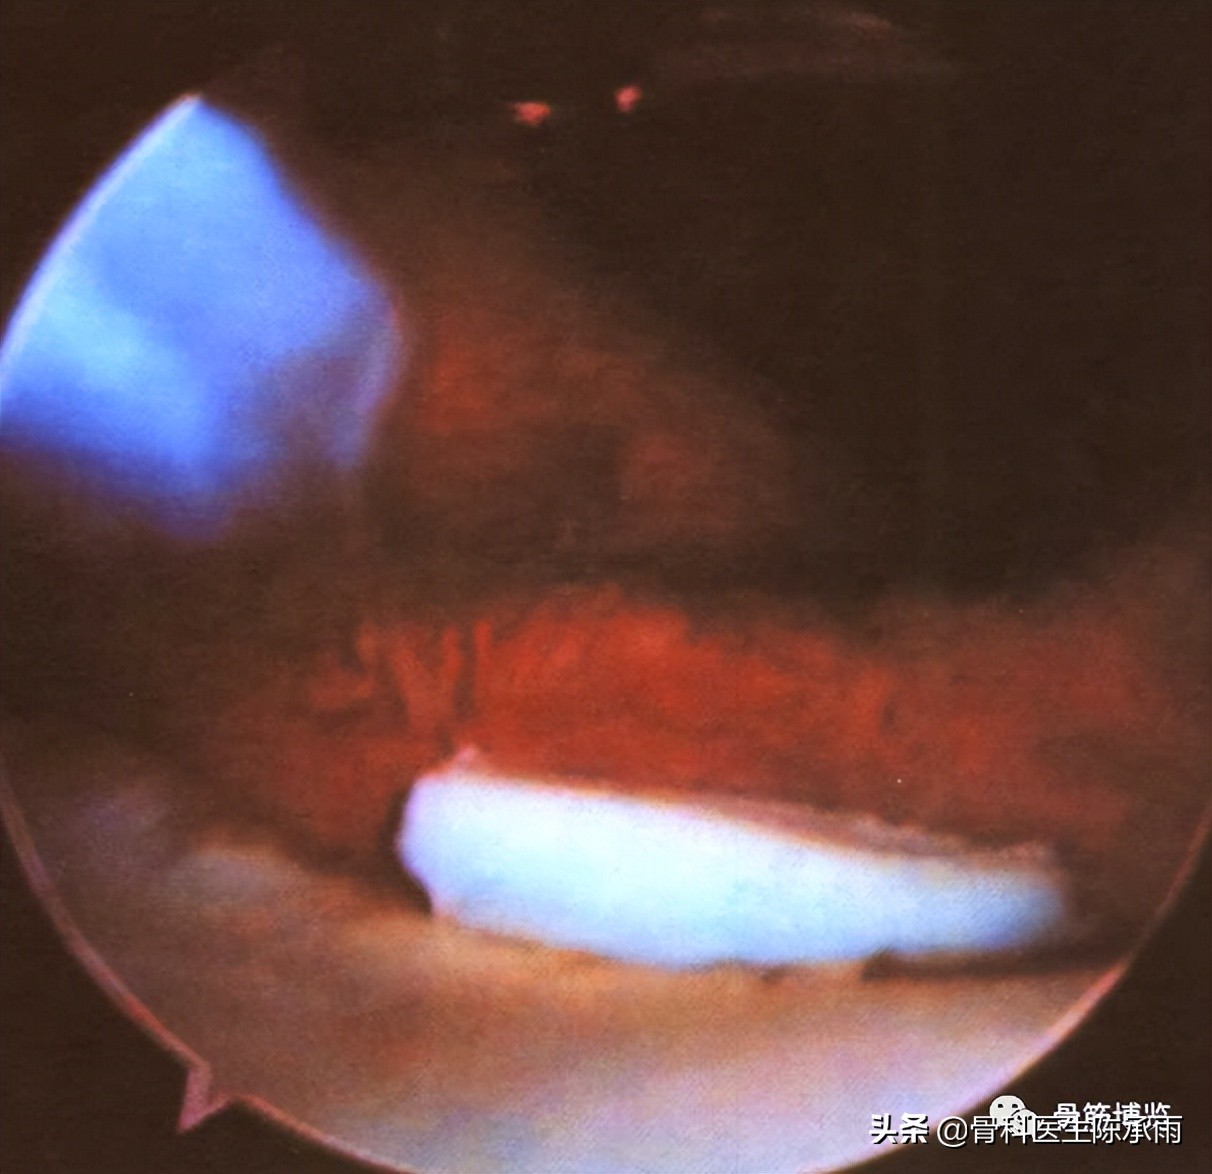

三、关节软骨损伤

急性膝关节损伤易造成关节软骨损伤,而软骨损伤在普通X光平片中又难以发现,给诊断造成困难。急性创伤性骸骨脱位易引起骸股关节软骨损伤及切线骨折。镜下检查可发现其损伤并进行处理;

关节骨软骨骨折块游离致髌上囊一游离体